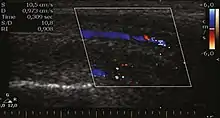

Venous drainage is performed by the deep and superficial dorsal veins of the penis. The dorsal arteries of the penis are located adjacent to the deep dorsal vein and a cavernous artery is located in the center of each corpus cavernosum. On color Doppler, the cavernous arteries present single phase flow. In the flaccid penis (Figure 3), the normal cavernous arteries show a systolic peak between 11 and 20 cm/s. At the beginning of erection, the systolic and diastolic flows undergo progressive increases. When vein occlusion begins, the diastolic flow decreases progressively, and once stiffness is established, it becomes negative.[1]